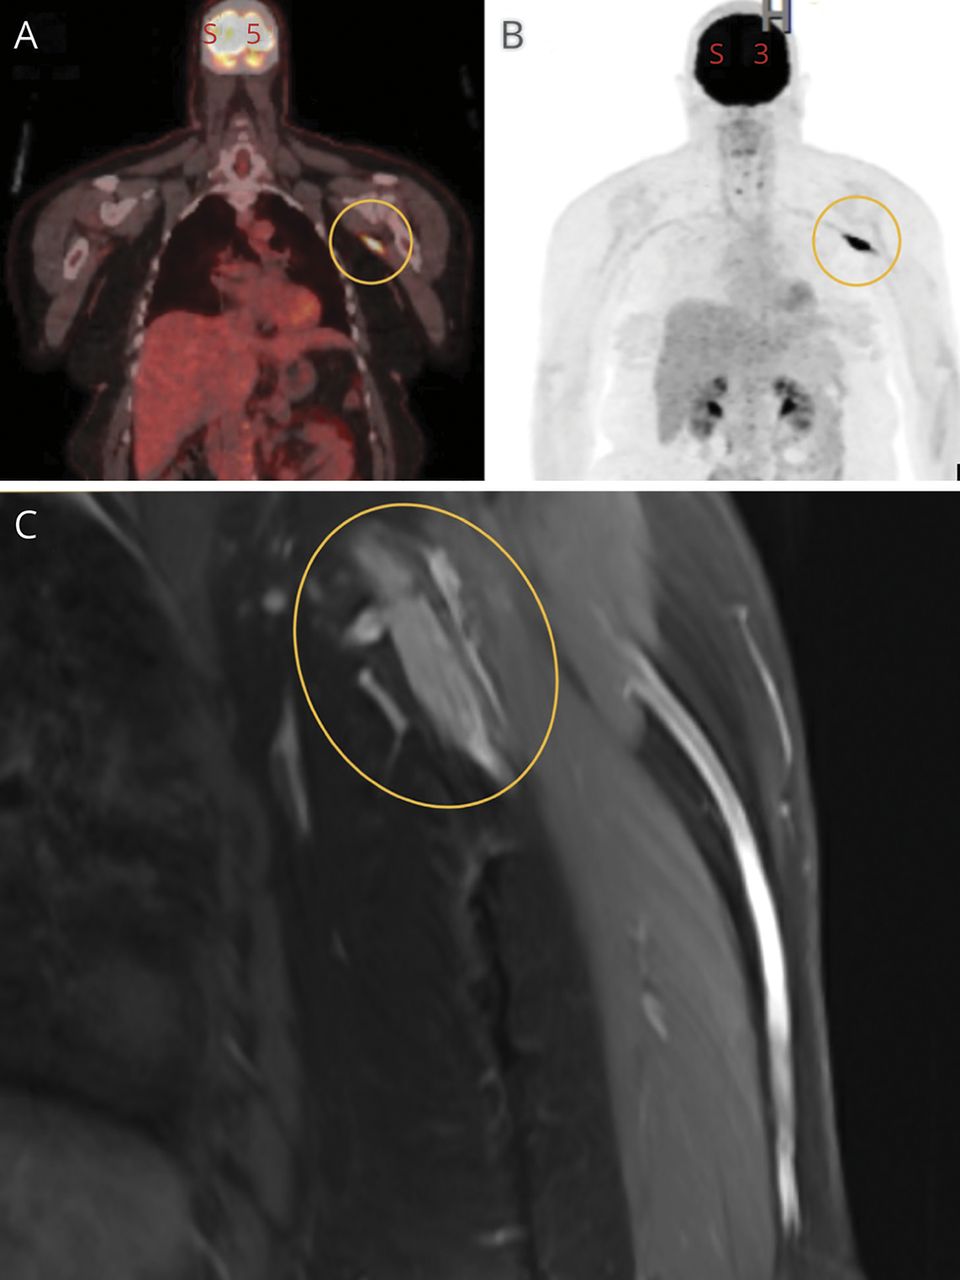

在我们的患者中,PET显示沿左腋窝血管束的线性摄取,这与上肢深静脉血栓形成(DVT)最一致。没有局灶性摄取提示肿瘤复发(图2).

在我们的病人,MRI显示增强,t2高信号左腋窝肿块。报告一例淋巴结肿大或神经鞘肿瘤的鉴别诊断(图2).

由于高度怀疑是肿瘤过程,我们决定进行开放性神经活检。从臂丛外侧束至桡神经近端切除肿块。组织学切片显示周围神经广泛弥漫性浸润,大量肿瘤淋巴样细胞团和片状浸润(图1;links.lww.com/WNL/C350).组织学结果与她的DLBCL复发一致。免疫染色显示淋巴样细胞为表达CD5、CD20、CD79a、MUM1和BCL2的B细胞,细胞周期蛋白D1、CD10、BCL6和MYC阴性(图2);links.lww.com/WNL/C350).骨髓活检、脊髓液和PET/CT扫描均未见恶性累及。